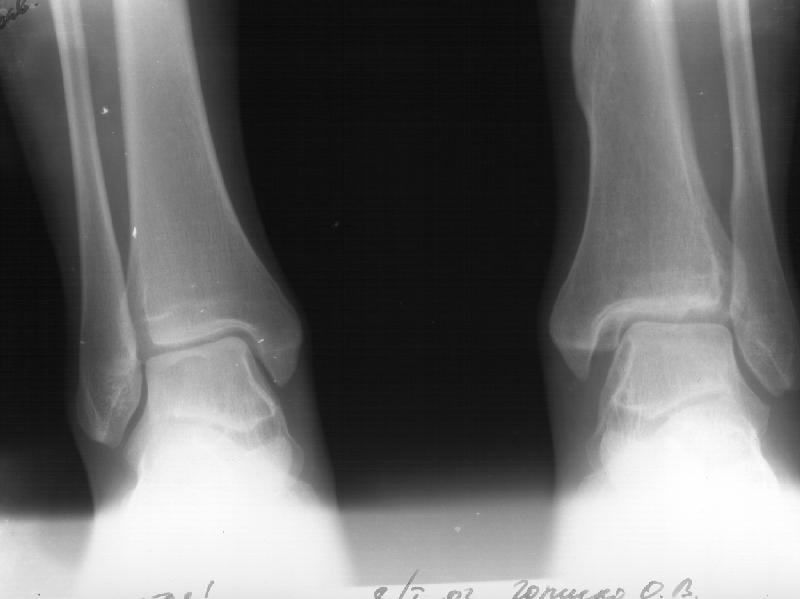

Девочка 14 лет полтора года назад оперирована в детской больнице по поводу спирального перелома костей голени (снимок 1)- выполнен закрытый остеосинтез стержнем Богданова, введенным ретроградно с медиальной стороны (снимок 2). Фиксатор после сращения удален

(см. снимки 3 и 4, после удаления, для сравнения со здоровой стороной, фас - стоя с нагрузкой на обе ноги). В настоящее время беспокоят боль и отеки в области голеностопного сустава при нагрузках, после ходьбы. В покое и ночью боли нет.Амплитуда движений в голеностопном суставе практически полная. Имеется заметная боковая нестабильность, т.е. несостоятельность дельтовидной связки и межберцоого синдесмоза. Складывается впечатление, что при остеосинтезе был отколот и смещен в сторону сустава костный фрагмент позади внутренней лодыжки, увеличилось смещение отломка заднего края, что привело к столь ранним проявлениям деформирующего артроза. Встает вопрос - что делать сейчас?Артодез - наверно, рано. Ревизию сустава, моделирующую резекцию?Пластику связок? Что-то еще? Заранее спасибо.